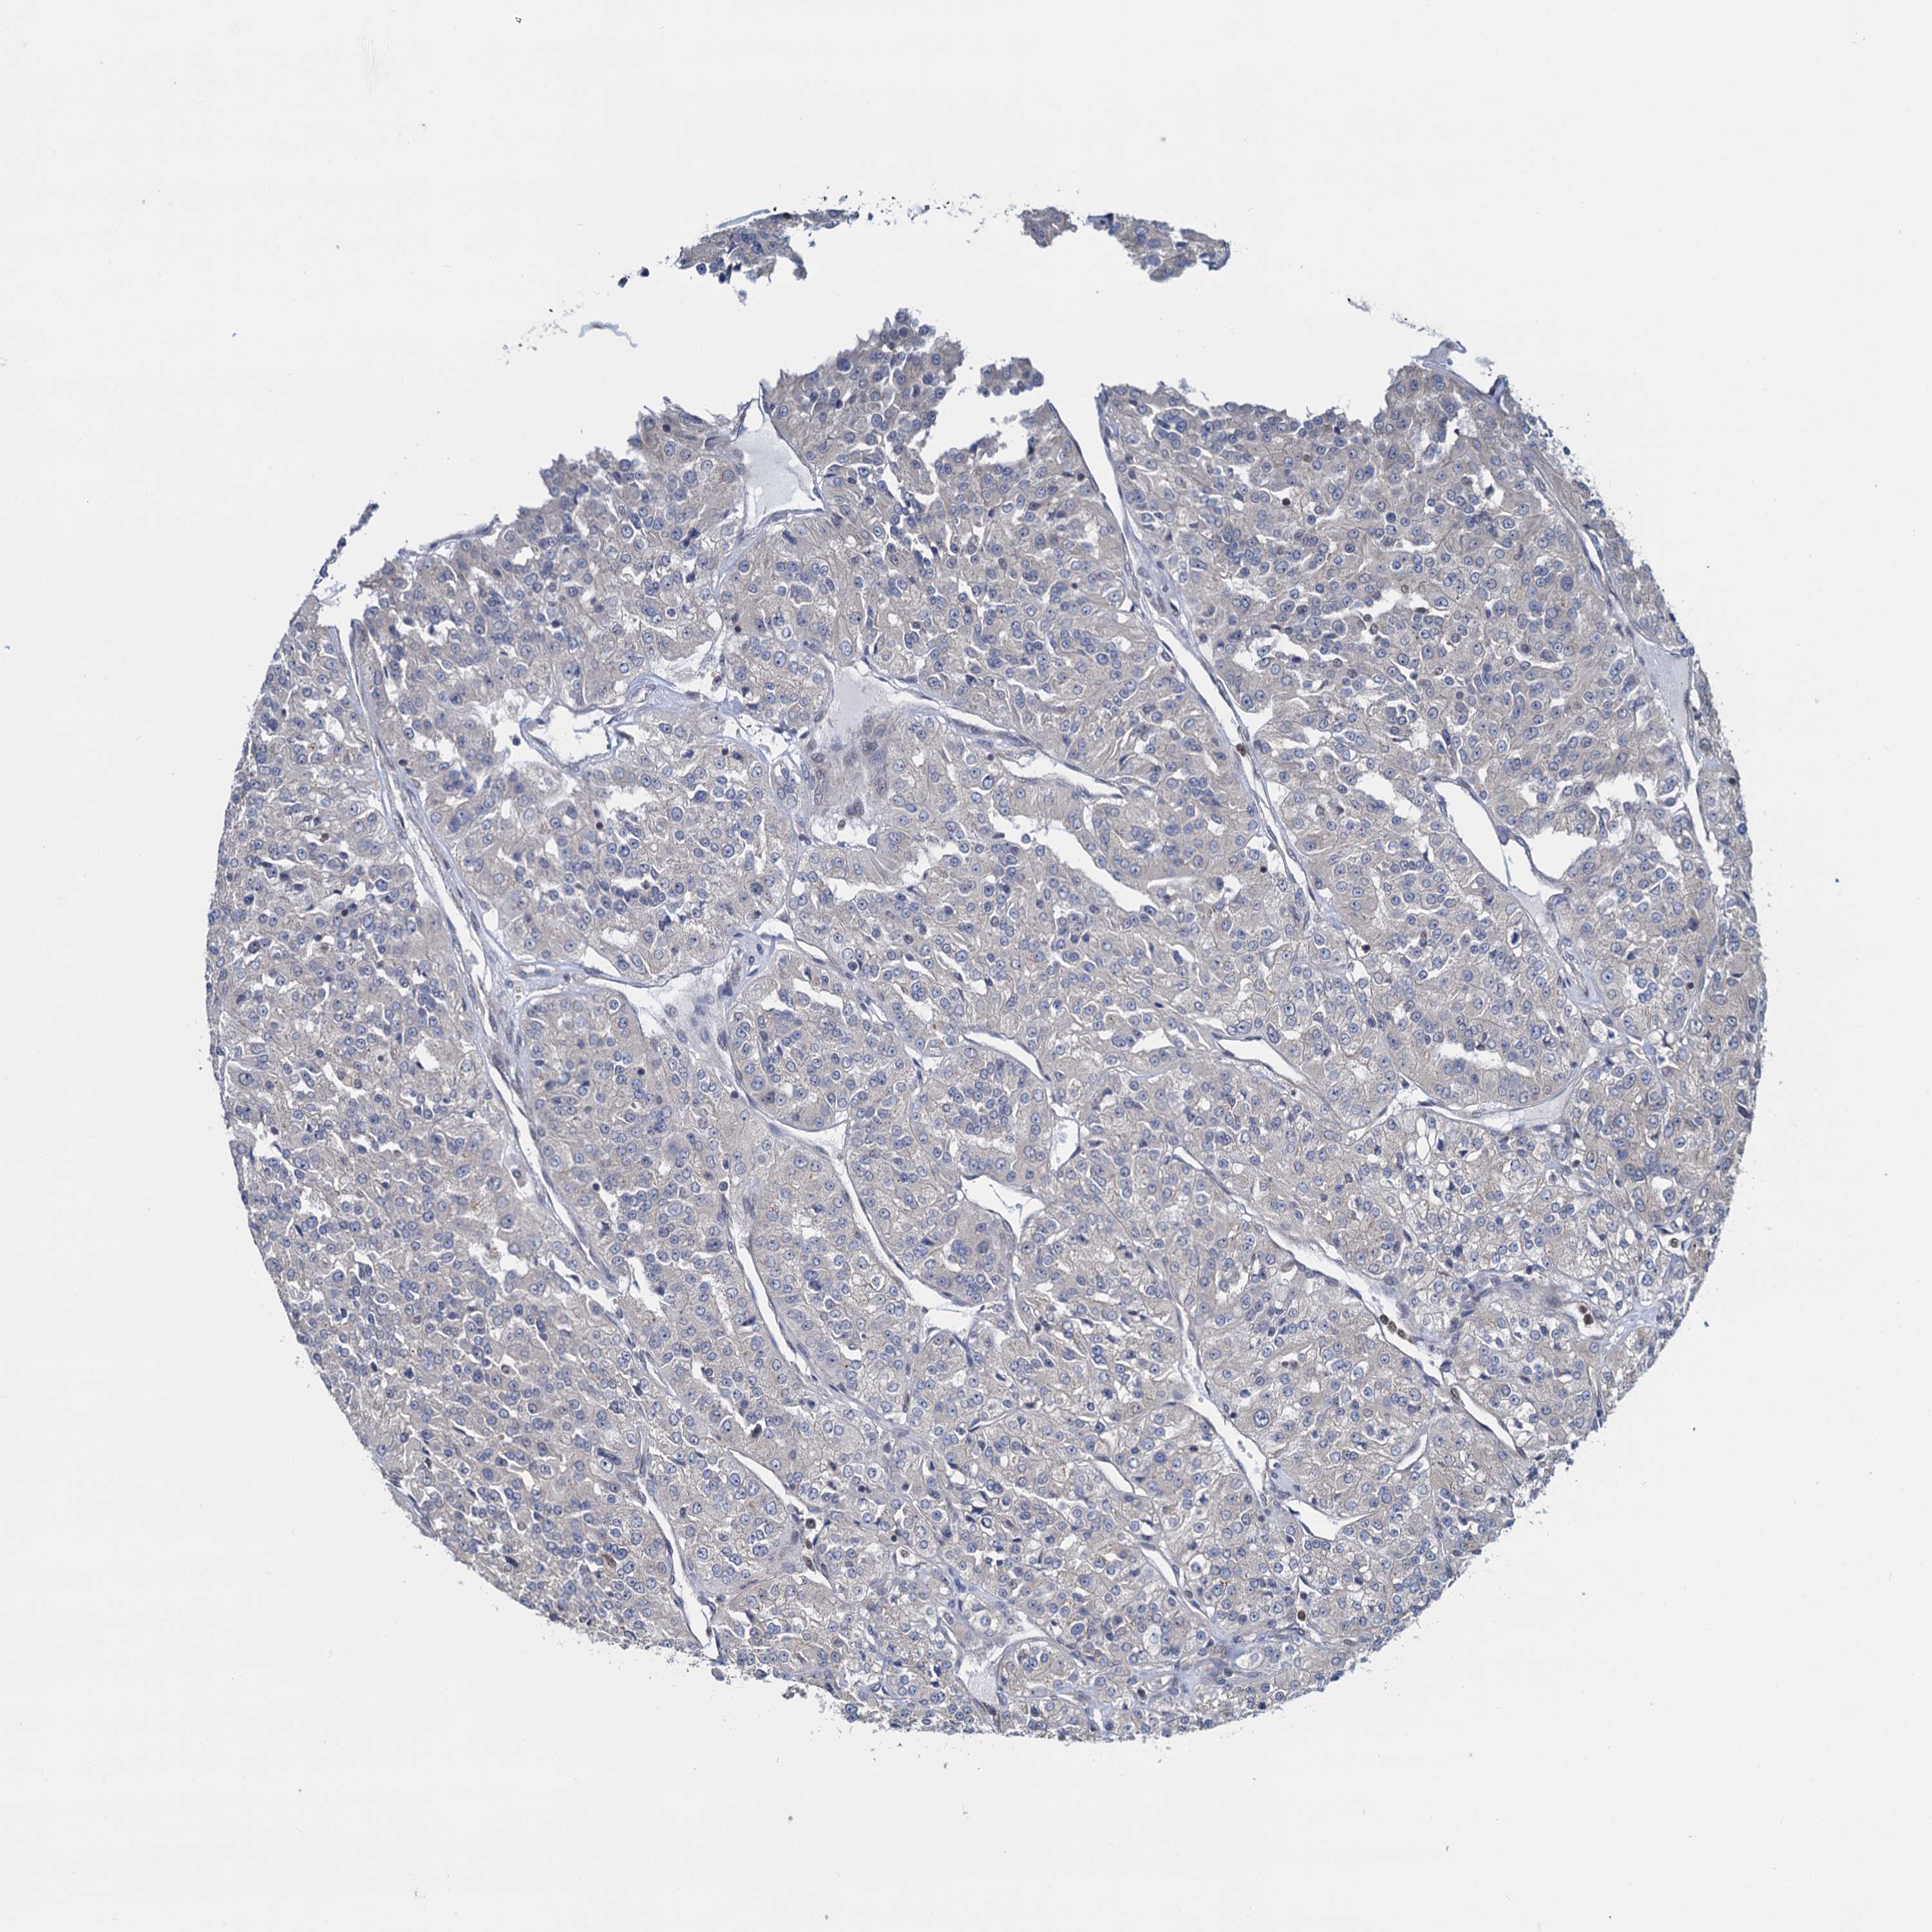

KIDNEY RENAL PAPILLARY CELL CARCINOMA (TCGA) - Interactive survival scatter ploti

The Survival Scatter plot shows the clinical status (i.e. dead or alive) for all individuals in the patient cohort, based on the same data that underlies the corresponding Kaplan-Meier plots. Patients that are alive at last time for follow-up are shown in blue and patients who have died during the study are shown in red.

The x-axis shows the expression levels (FPKM) of the investigated gene in the tumor tissue at the time of diagnosis. The y-axis shows the follow-up time after diagnosis (years). Both axes are complimented with kernel density curves demonstrating the data density over the axes. The top density plot shows the expression levels (FPKM) distribution among dead (red) and alive patients (blue). The right density plot shows the data density of the survived years of dead patients with high and low expression levels respectively, stratified using the cutoff indicated by the vertical dashed line through the Survival Scatter plot. This cutoff is automatically defined based on the FPKM cutoff that minimizes the p-score. The cutoff can be changed by dragging the vertical line or by entering a cutoff value in the square labeled "Current cut-off".

Under the Survival Scatter plot the p-score landscape (black curve; left axis) is shown together with dead median separation (red curve; right axis). Dead median separation is the difference in median mRNA expression between patients who have died with high and low expression, respectively. It is calculated as follows: median FPKM expression of dead patients with high expression - median FPKM expression of dead patients with low expression. This is intended to aid the user in visually exploring custom cutoffs and the associated p-scores and dead median separation.

Individual patient data is displayed and can be filtered by clicking on one or more of the category buttons on the top of the page. Categories describing expression level and patient information include: high, low, alive, dead, female, male and tumor stages. The scale of the x-axis can be toggled between linear and log-scale by clicking on the "x log" button. Mouse-over function shows TCGA ID, patient information and mRNA expression (FPKM) for each patient.

& Survival analysisi

Kaplan-Meier plots summarize results from analysis of correlation between mRNA expression level and patient survival. Patients were divided based on level of expression into one of the two groups "low" (under cut off) or "high" (over cut off). X-axis shows time for survival (years) and y-axis shows the probability of survival, where 1.0 corresponds to 100 percent.

RNF125 is not prognostic in Kidney Renal Papillary Cell Carcinoma (TCGA)

Best expression cut offi

: 1.09